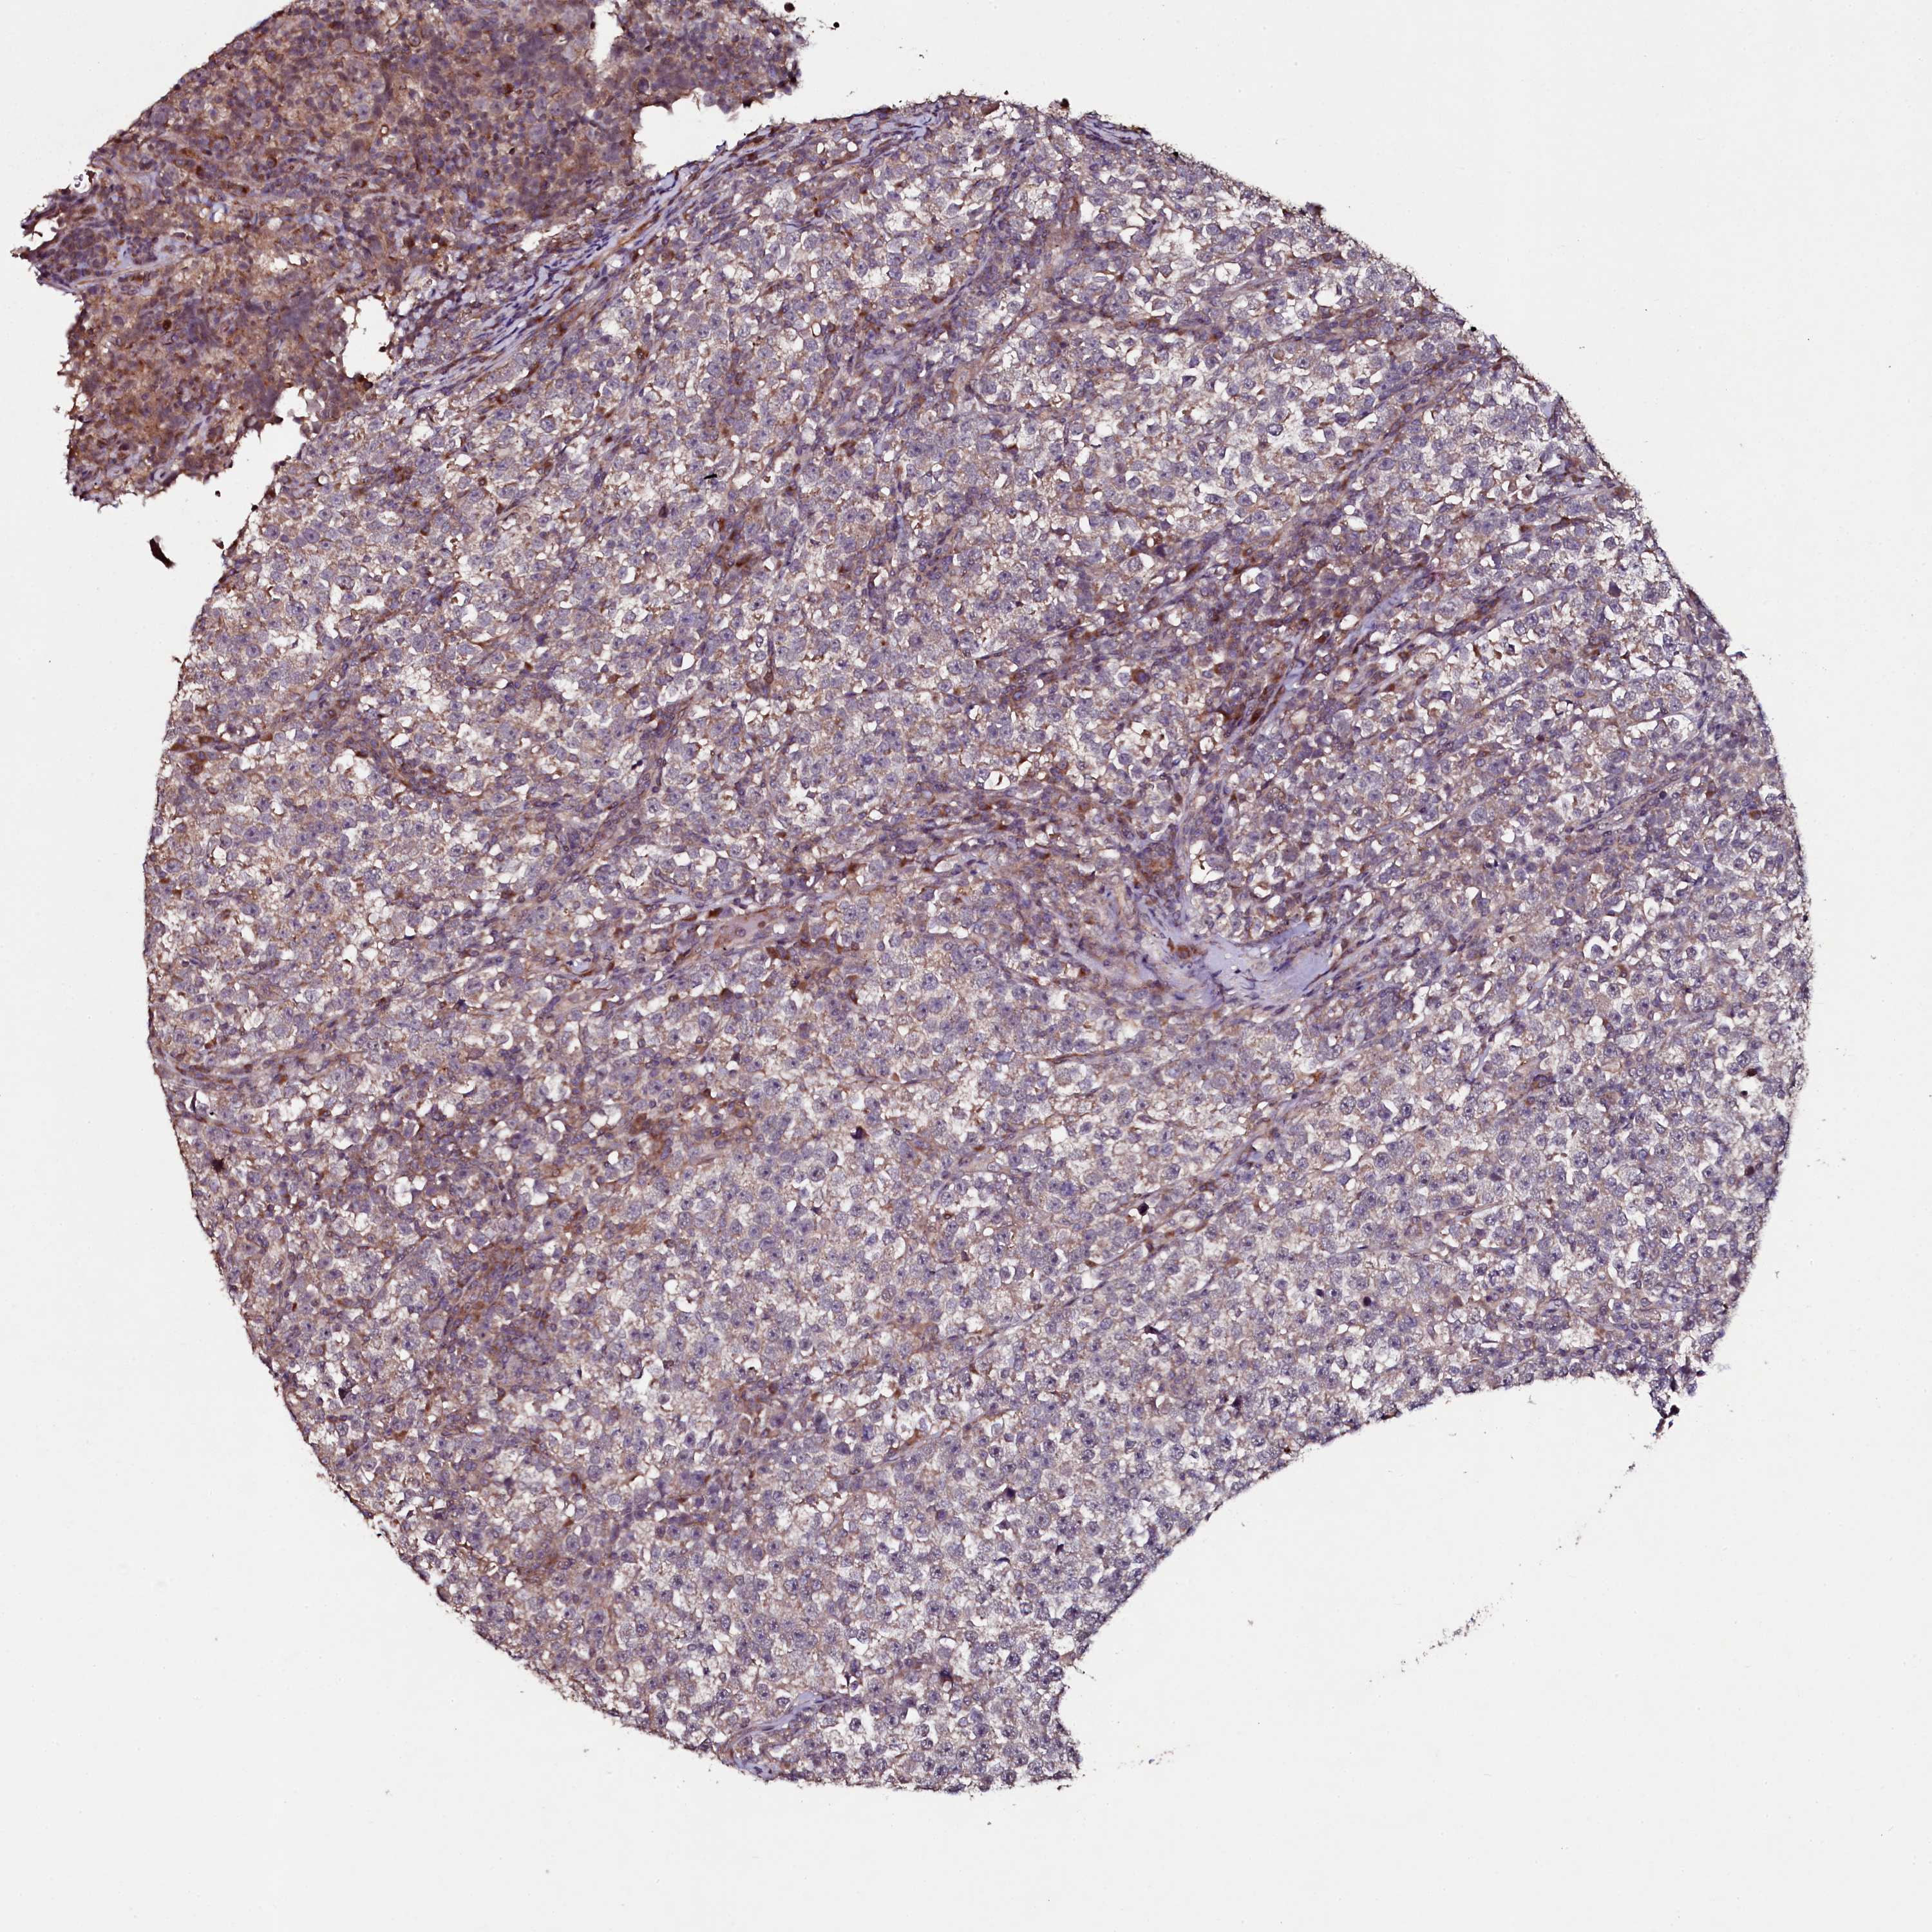

TESTIS CANCER - Protein expressioni

A mouse-over function shows sample information and annotation data. Click on an image to view it in a full screen mode. Samples can be filtered based on level of antibody staining by selecting one or several of the following categories: high, medium, low and not detected. The assay and annotation is described here.

Note that samples used for immunohistochemistry by the Human Protein Atlas do not correspond to samples in the TCGA dataset.

Antibody stainingi

Antibody staining in the annotated cell types in the current human tissue is reported as not detected, low, medium, or high, based on conventional immunohistochemistry profiling in selected tissues. This score is based on the combination of the staining intensity and fraction of stained cells.

Each image is clickable and will lead to virtual microscopy that enables deeper exploration of all samples and also displays staining intensity scores, fraction scores and subcellular localization as well as patient and tissue information for each sample.

Antibody HPA040196

Antibody HPA040213

Urothelial carcinoma, High grade

Seminoma, NOS

Carcinoma, Embryonal, NOS